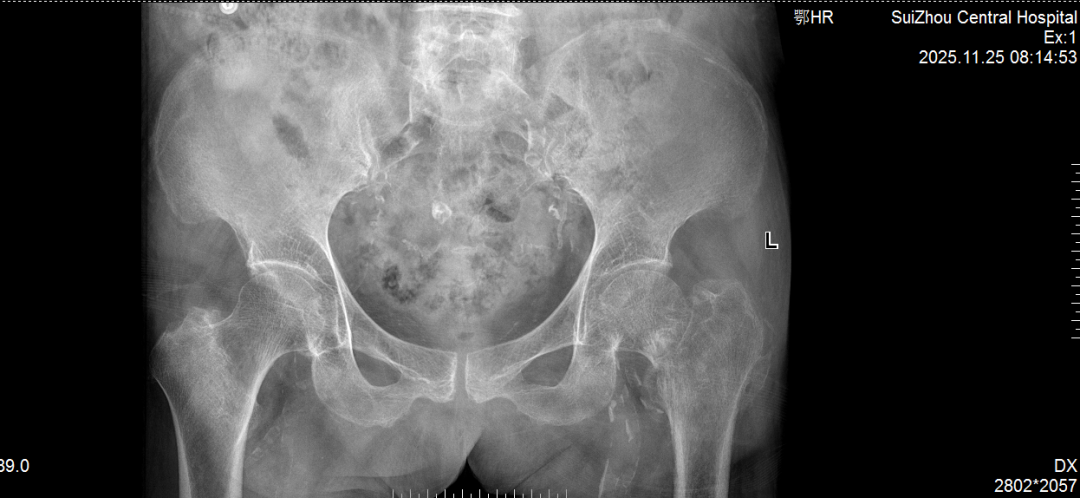

术前术后